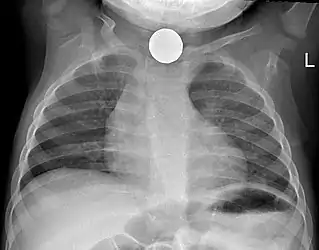

Non-invasive testing

Prior to undertaking endoscopy, attempts should be made to locate the foreign body with x-rays or other non-invasive techniques.[1] For radio-opaque objects, x-rays of the neck, chest and abdomen can be used to locate the foreign body and assist endoscopy.[9] Alternative approaches, including the use of metal detectors, have also been described.[10]

X-rays are also useful for identifying the type of foreign body ingested and complications of foreign body ingestion, including mediastinitis and perforation of the esophagus.[1]